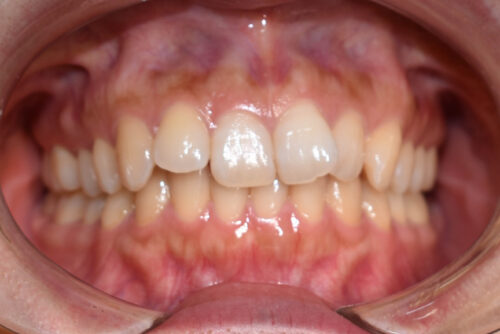

ワイヤー矯正治療10か月後です。

ワイヤー期間 10か月, 14回来院

本症例も

上顎左右臼歯部に

歯科矯正用アンカースクリュー(デュアル・トップオートスクリュー)を用い

下あごを オートローテーションさせ

また 上下の歯列全体を

後方へ移動させることで

歯を抜かなくても

口元の改善も行いました。

上下の正中には 若干ずれが残存しましたが、

かみ合わせ重視で

終了いたしました。